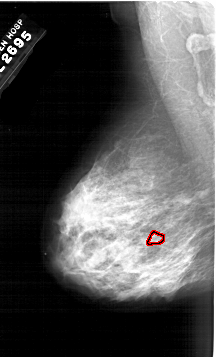

A_1983_1.LEFT_MLO

LEFT_MLO LINES 6421 PIXELS_PER_LINE 3886 BITS_PER_PIXEL 12 RESOLUTION 43.5 OVERLAY

FILE: A_1983_1.LEFT_MLO.OVERLAY

TOTAL_ABNORMALITIES 1

ABNORMALITY 1

LESION_TYPE CALCIFICATION TYPE PUNCTATE DISTRIBUTION CLUSTERED

ASSESSMENT 4

SUBTLETY 1

PATHOLOGY MALIGNANT

TOTAL_OUTLINES 1

BOUNDARY